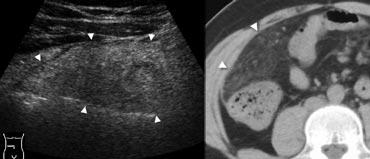

Hình 8. Nam giới 41 tuổi bị nhồi máu mạc nối. A, Siêu âm vùng bụng phải giữa cho thấy một vùng mỡ phúc mạc viêm rộng (đầu mũi tên). B, CT không tiêm thuốc cản quang mô tả tổn thương là một vùng mỡ mạc nối viêm dạng bánh (đầu mũi tên), lớn hơn so với viêm túi mỡ đại tràng và không có vòng tăng tỷ trọng.

Nhồi máu mạc nối

Nhồi máu mạc nối có sinh lý bệnh và biểu hiện lâm sàng tương tự viêm túi mỡ đại tràng, với mô mỡ bị nhồi máu là một đoạn mạc nối bên phải. Hình ảnh cho thấy một khối mỡ viêm dạng bánh (Hình 8), lớn hơn so với viêm túi mỡ đại tràng và không có vòng tăng tỷ trọng trên CT.

Hình 9. Nữ giới 47 tuổi với đau hố chậu phải cấp tính. CT không tiêm thuốc cản quang cho thấy một khối mỡ viêm hình bầu dục (đầu mũi tên) với các quai ruột lân cận bình thường. Hình dạng và kích thước của tổn thương gợi ý viêm túi mỡ đại tràng, nhưng tổn thương không chứa vòng tăng tỷ trọng. Trong trường hợp này, khó phân biệt giữa viêm túi mỡ đại tràng hay nhồi máu mạc nối nhỏ.

Trong một số trường hợp, có thể khó phân biệt viêm túi mỡ đại tràng với nh